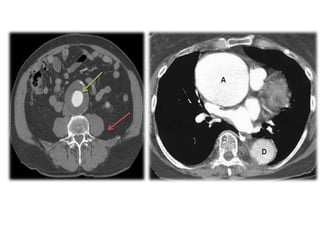

The diagnosis of the case is : Atherosclerotic AAA .

Second Case A 65-year-oldman has sudden onset of severe abdominal pain. Physical examination reveals his temperature is 37 C, heart rate 110/minute, respirations 25/minute, and blood pressure 145/100 mmHg. He has diminished pulses in the lower extremities. There is a pulsatile abdominal mass. His serum creatine kinase is not elevated. He has had fasting blood glucose measurements in the range of 180 to 220 mg/dL for over 20 years. What is your medical diagnosis? HR: 60-80 bpm. RR:12-18 pbm. Glucose: 110-125 mg/dl

The diagnosis ofthe case is : Atherosclerotic AAA . What is aneurysm ? a general term for any swelling (dilation) of the aorta to greater than 1.5 times normal. Usually representing an underlying weakness in the wall of the aorta at that location. How does patient feel? Abdominal Aortic Aneurysms Most (AAAs) develop slowly over years. They often don't cause signs or symptoms unless they rupture. When symptoms are present, they can include: A throbbing feeling in the abdomen. Deep pain in the back or the side of the abdomen that lasts for hours or days. Thoracic Aortic Aneurysms Symptoms may include: Pain in the jaw, neck, back, or chest . Coughing and/or hoarseness. Shortness of breath and/or trouble breathing or swallowing.

What about diagnosis? Ultrasound and Echocardiography ,CT ,MRI ,Angiography. Treatment? Medicines Medicines are used to lower blood pressure, relax blood vessels, and lower the risk that the aneurysm will rupture (burst). Beta blockers and calcium channel blockers are the medicines most commonly used. Surgery The two main types of surgery to repair aortic aneurysms are open abdominal or open chest repair and endovascular repair.